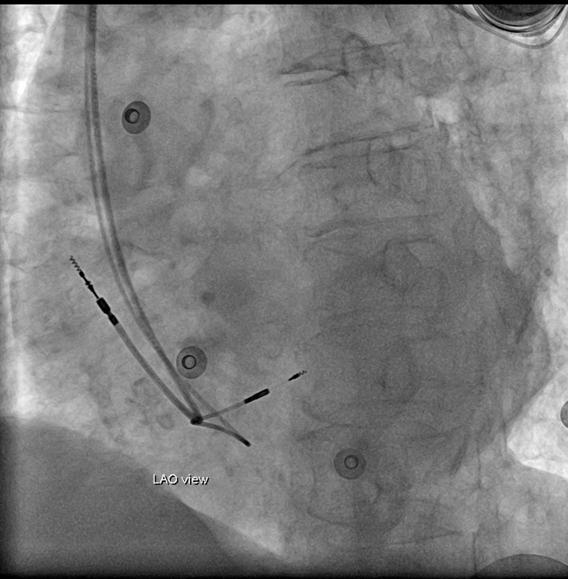

在筆者服務的醫院流程,對於希氏束心臟節律器 或是左束支區域心臟節律器的置放都是使用 C315 導管 與 3830 導線。由於希氏束心臟節律器的種種限制,左 束支區域心臟節律器的置放較為普及。當 3830 導線在 放射線導引下置放於左心室中膈時,首先會觀察是否 有記錄到左束支訊號 (left fascicular potential) ( 圖一 ) 。

另外在該位置進行電擊刺激,倘若能夠於 V1 導程記錄

到以V1波的谷底為中心,呈現典型的"w" 形圖案則更加

確認最理想的位置。除了電生理表現外,在左前斜視

角 (left anterior oblique) 的放射線影像下,我們也會確

認 3830 導線是否垂直於心室中膈與注射顯影劑以評估

3830 導線進入心室中膈的深度 ( 圖二 ) 。左束支傳導心

臟節律器心電圖如 ( 圖三 ) 所示,節律器術後追蹤時於 部分病人可見fascicular potential確認有bundle capture。

(圖四)

(圖二) (圖三) (圖四) 中華民國心律醫學 會 Taiwan